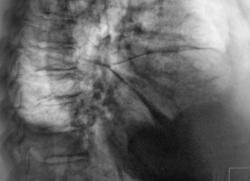

Цирротический туберкулёз верхней доли правого лёгкого со смещением органов средостения. Случай верифицирован (вскрытие).